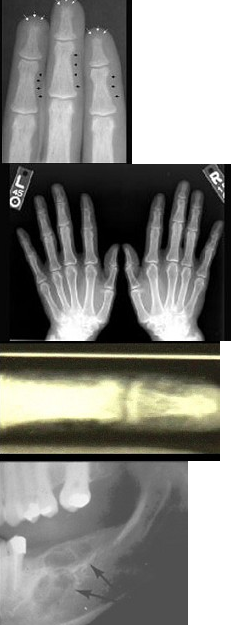

女性,50岁,反复发作尿路结石,骨痛,骨骼X线示骨膜下皮质吸收。实验室检查:高钙血症,血清碱性磷酸酶↑,皮质醇抑制试验血清钙不下降。诊断考虑( )

A:原发性甲状旁腺功能亢进症